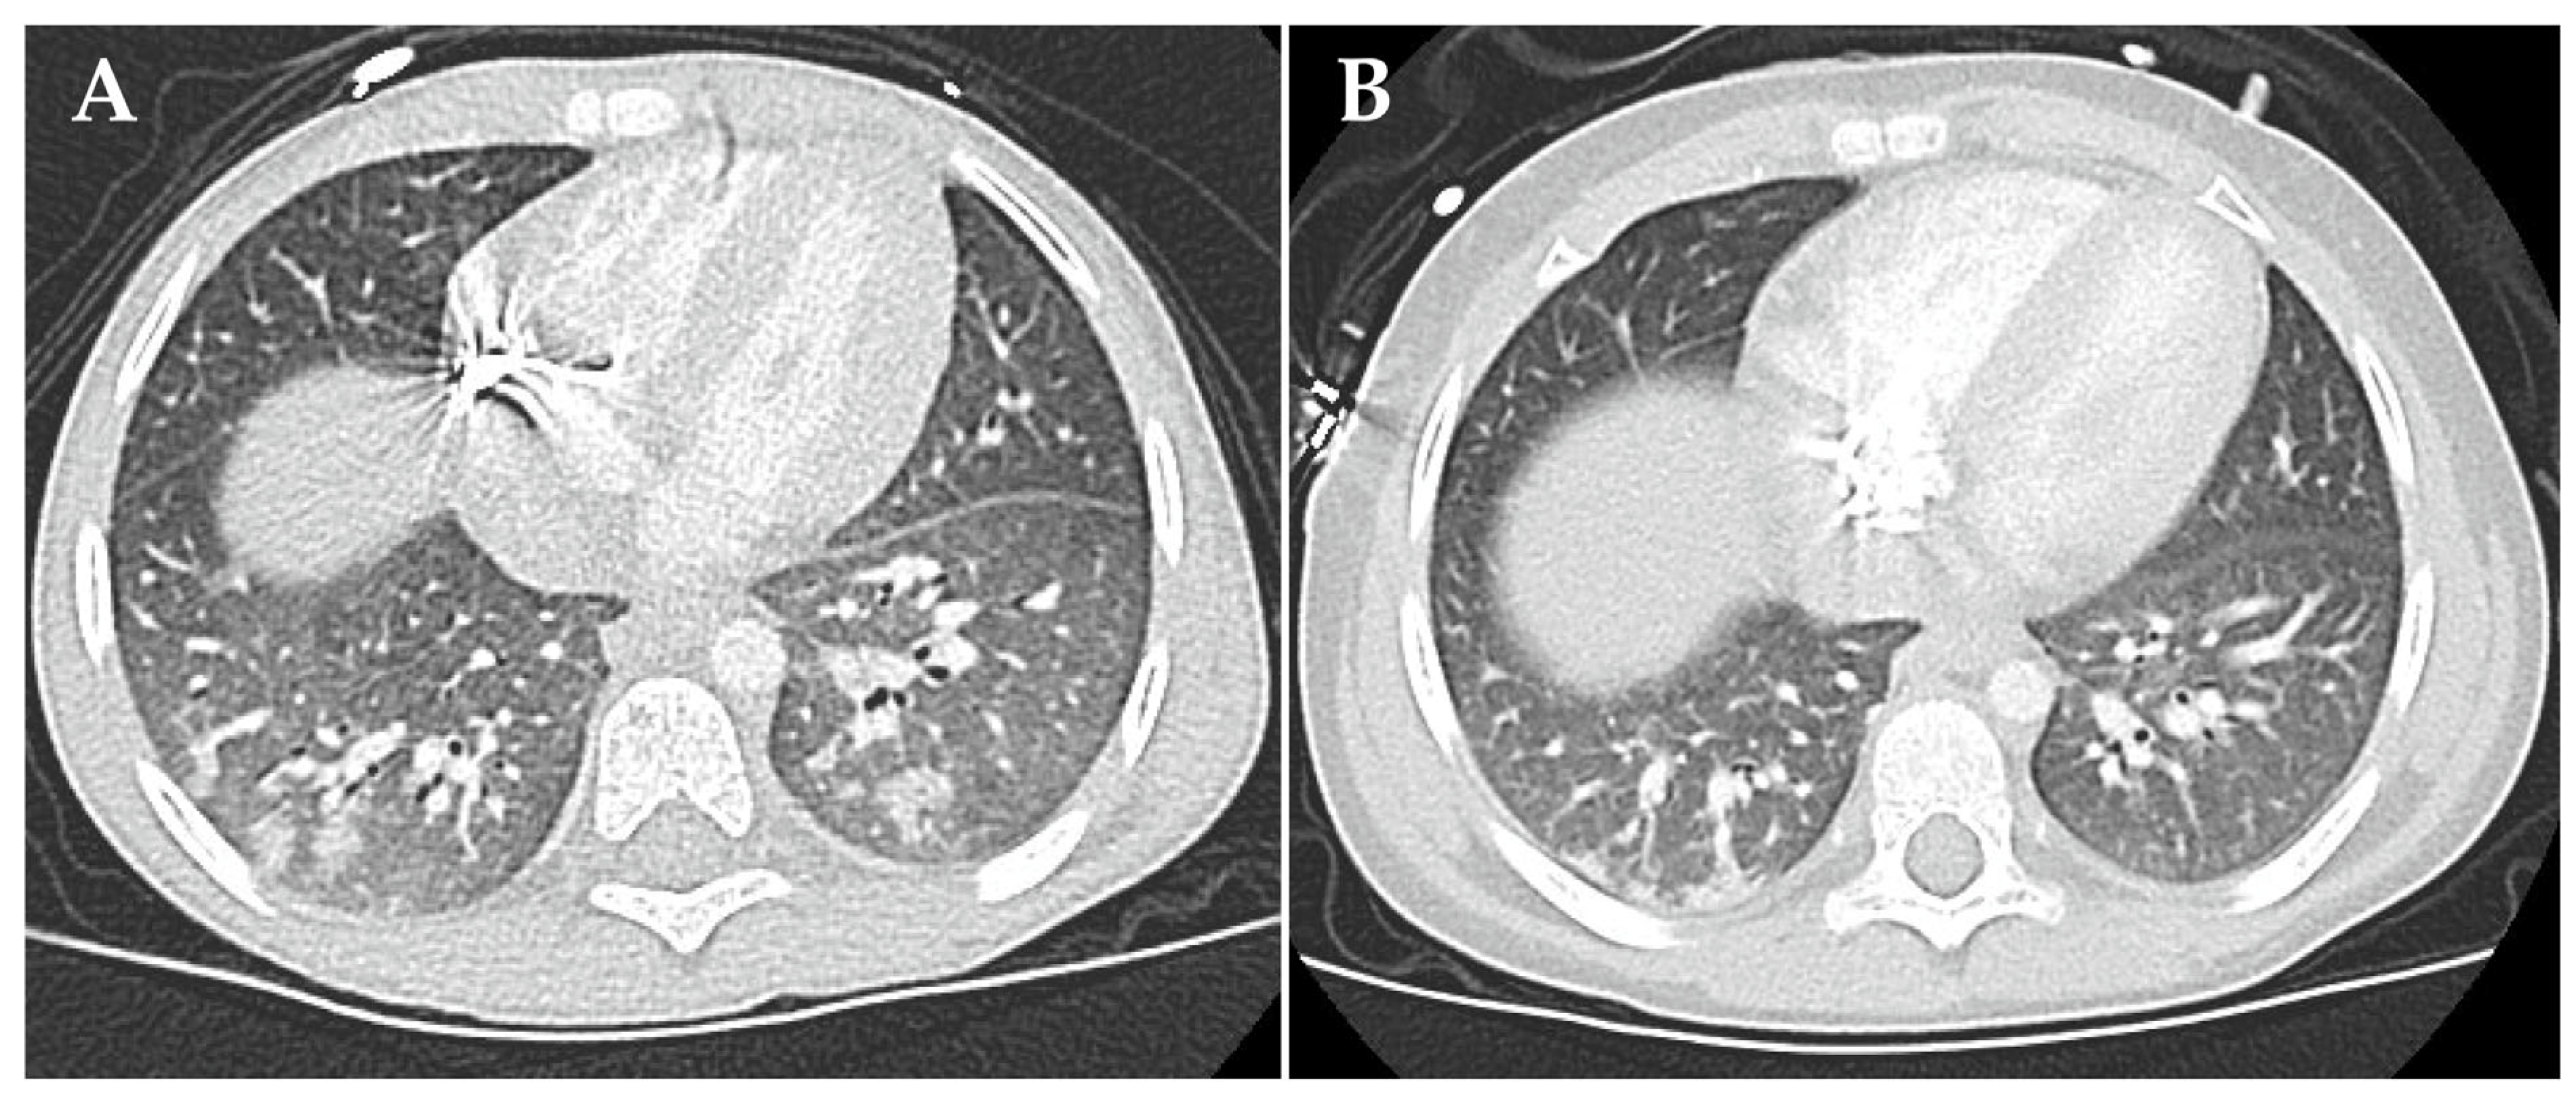

On day +74, respiratory failure with rapidly evolving tachydyspnoea recurred. The chest X-ray now demonstrated bilateral pulmonary infiltrates and pleural effusions (Figure 2B). Patient 1 was re-intubated and placed on IMV as an emergency measure for 6 days. Systemic inflammatory parameters were again high but without a causal pathogen (extensive testing). Empiric antibiotic and antifungal regimens were nevertheless applied. High-resolution computed tomography (HRCT) showed increased ground-glass opacification and consolidation, particularly in both lower lobes (Figure 3A). Busulfan-induced lung injury was the leading differential diagnosis at this stage, and a methylprednisolone pulse was administered (Figure 1). This anti-inflammatory therapy improved the respiratory situation, eventually enabling successful extubation. Patient 1 required non-invasive ventilation followed by high-flow nasal cannula therapy and continuous oxygen supplementation via a nasal cannula for 20 months (Figure 1).

Figure 3.

High-resolution computed tomography findings of busulfan-induced lung injury in patient 1 at diagnosis (A) and at follow-up eight months after start of the anti-inflammatory and immunomodulatory therapy (B).

Treatment of busulfan-induced lung injury included a total of eight methylprednisolone pulses and continuous prednisolone therapy at a dose of 2 mg/kg/d, which could only be tapered from month 4 onwards (Figure 1). The systemic corticosteroid therapy, causing the full spectrum of Cushing’s disease, was combined with inhalative corticosteroids, inhalative short-acting β-agonists and oral azithromycin therapy in line with the graft-versus-host lung stage 1 treatment protocol used in the allogeneic setting, as we considered the evidence for successful anti-inflammatory therapy of the lung high when following these recommendations. In total, 15 cycles of extracorporal photopheresis were also performed to employ its immunomodulatory effects [13,14,15] against the as yet not fully understood molecular cascades causing lung injury (Figure 1). HRCT performed at 8 months after the clinical onset of busulfan-induced lung injury showed that the consolidation had resolved (Figure 3B). Spirometry presented a restrictive pattern with stepwise amelioration over time. To delay the potential initiation and progression of fibrotic processes in the lung, oral therapy with the small-molecule tyrosine kinase inhibitor, nintedanib, was administered for 3 months [16]. The patient fully recovered with no remaining signs of busulfan-induced lung injury in spirometry. Standard oncological therapy (radiotherapy of the preoperative thoracic tumor bed followed by immunotherapy) could not be administered. Therefore, four cycles of RIST therapy (NCT01467986) were administered as a bridging therapy, which needed to be discontinued to treat infectious complications, most likely due to the extended immunosuppression caused by the combination with corticosteroid therapy. Patient 1 resumed standard oncological therapy after recovery from the busulfan-induced lung injury and tolerated the dinutuximab beta-based maintenance therapy very well.

At day +52 after autologous stem cell transplantation, patient 2 developed partial respiratory failure with dyspnea and need for continuous low-level oxygen. The chest X-ray showed moderate bilateral infiltrates and pulmonary venous congestion. HRCT imaging revealed atypical pneumonic changes, characterized by ground-glass opacification and patchy consolidation in the lower lobes (Figure 5A). An empirical antibiotic and antifungal therapy was initiated. No pathogen was identified in a comprehensive infectious diagnostic work-up. At disease onset, radiological signs and echocardiographic findings did not suggest pulmonary veno-occlusive disease. Systemic prednisolone therapy (2 mg/kg/d) stabilized respiratory status. Topical treatment comprising inhalative corticosteroids and short-acting β-agonists in combination with azithromycin was initiated. Patient 2 required continuous oxygen supplementation for 6 months (Figure 4). A modified version of the four-compound RIST therapy (NCT01467986, experimental arm; dasatinib multityrosine kinase inhibitor substituted by the third-generation ALK tyrosine kinase inhibitor, lorlatinib) was employed as a bridging oncological therapy for 6 months. The therapy was paused according to standard oncological procedures in case of (respiratory tract) infections. HRCT findings 6 months after partial respiratory failure onset showed regression of consolidations and opacities and no evidence of pulmonary fibrosis (Figure 5B). Patient 2 resumed and completed the standard oncological treatment regimen and has remained in first complete remission until the date of publication (Figure 4).

Figure 5.

High-resolution computed tomography findings of busulfan-induced lung injury in patient 2 at diagnosis (A) and six months after start of the anti-inflammatory therapy (B). (A) Shown are atypical pneumonic changes, characterized by ground-glass opacification and patchy consolidation in the lower lobes. (B) Shown is the regression of consolidations and opacities. There is no evidence of pulmonary fibrosis.